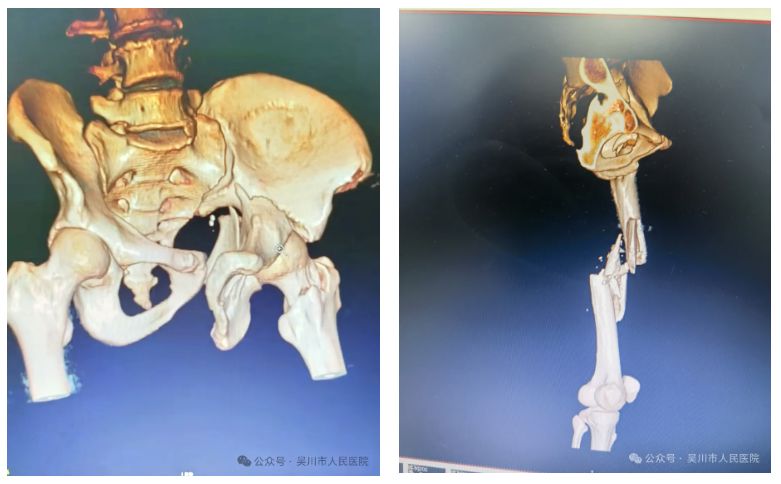

一名因车祸导致全身多处严重创伤的患者被送至我院时,已处于意识模糊、血压骤降的危险状态,诊断为多发性骨盆及股骨粉碎性骨折,伴有失血性休克,生命垂危。

创伤中心立即启动应急机制,急诊医学科迅速开通创伤绿色通道,院领导现场指挥调度,骨外科一区、麻醉科、重症医学科、输血科等多学科团队迅速集结,投入抢救。

医护团队果断采取“先保命,再治伤”的阶梯方案:先行骨科干预稳定骨折、控制出血,快速输血补液纠正休克,待生命体征平稳后,再行精准复位内固定手术。由曾文晓副主任医师、王井旺主治医师、李斌医师组成的手术团队争分夺秒、高效协作,顺利完成手术。术后患者转入ICU严密监护,经个性化治疗与护理,现已脱离生命危险,正在逐步康复中。